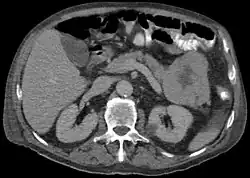

CT scan in a patient with acinar cell carcinoma

The disease is more common in men than women and the average age at diagnosis is about 60.[2] Symptoms are often non-specific and include weight loss. A classic presentation, found in around 15% of cases includes subcutaneous nodules (due to fat necrosis) and arthralgias, caused by a release of lipase.[2]